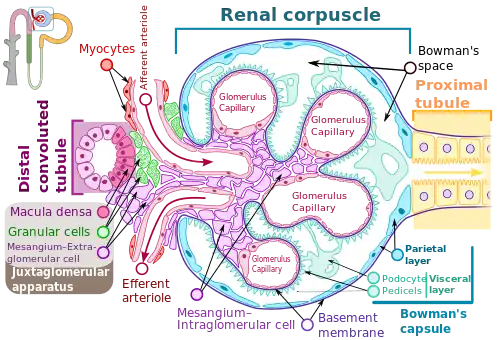

Membranoproliferative glomerulonephritis (MPGN) is a type of glomerulonephritis caused by deposits in the kidney glomerular mesangium and basement membrane (GBM) thickening,[2] activating the complement system and damaging the glomeruli.

Membranoproliferative glomerulonephritis involves deposits at the intraglomerular mesangium.